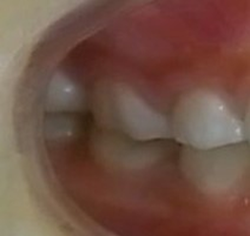

はじめに目立たないブラケット(歯に付ける矯正装置)を利用して上顎から歯並びを改善します。その折に同時にレジンを利用する事で咬み合わせの高さも挙上していきます。

歯並びを改善すると受け口がひどく見える時もありますが心配ありません。

次にMEAW(マルチループ)を利用する事で咬み合わせの高さや咬み合う平面の角度を変える事で歯(第一小臼歯)を抜く事無く受け口(下顎前突)を改善していきます。

また、MEAW(マルチループ)はゴムを24時間使用する事で最大の効果を発揮することが出来ます。